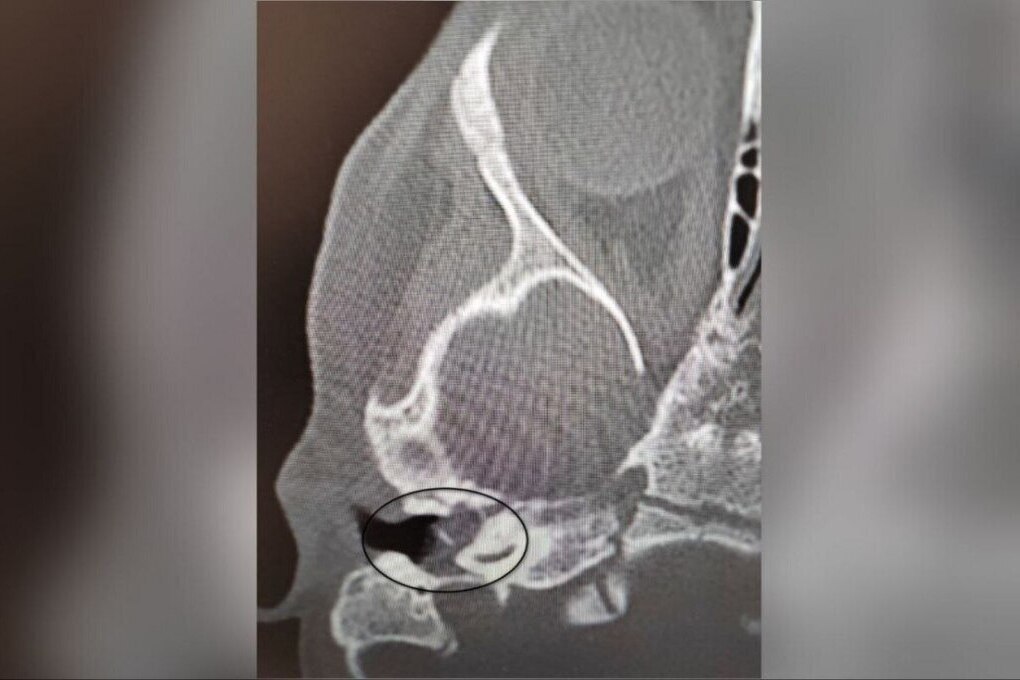

Специалисты Воронежской областной детской клинической больницы успешно провели уникальную операцию. Двухлетней девочке с редким заболеванием "врожденная холестеатома" не только спасли жизнь, но и восстановили слух. Об этом сообщили в пресс-службе регионального Министерства здравоохранения.

Проблемы начались после обычного ОРВИ, когда у ребенка появились боли в ухе. Ситуация усугубилась развитием пареза лицевого нерва, из-за чего ослабли мимические мышцы. Проведенное обследование подтвердило диагноз: врожденное кистозное образование в среднем ухе. Для сохранения здоровья и слуха девочки требовалось экстренное хирургическое вмешательство.

Операцию провел Антон Мащенко, заведующий отделением больницы. Во время сложной процедуры врачи удалили кистозное образование, восстановили функцию лицевого нерва и систему звукопроведения, что позволило не только устранить угрозу, но и сохранить слух ребенка.